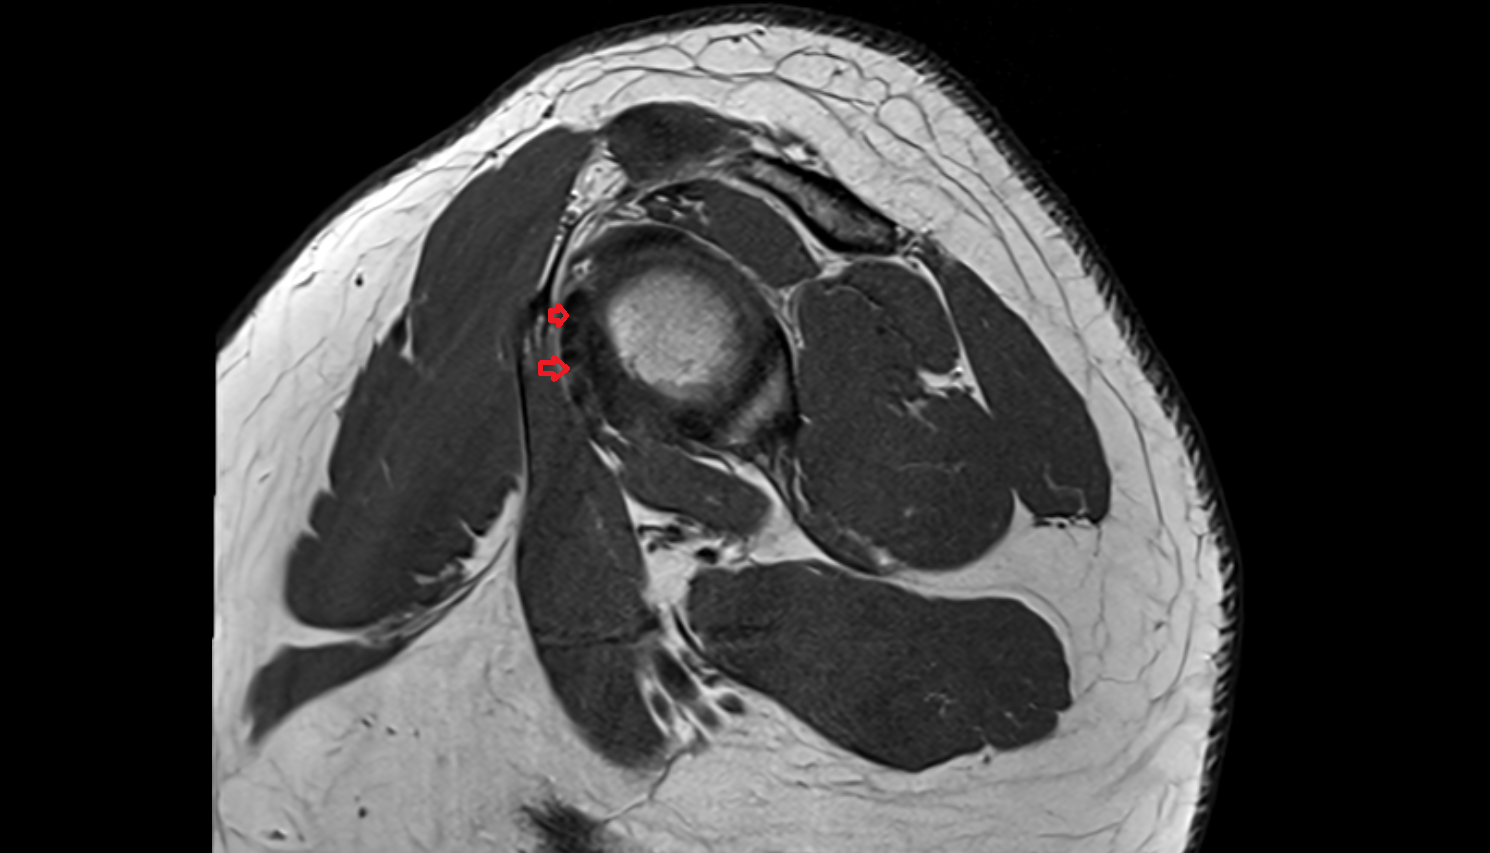

- Subscapularis tendon

- Glenoid labrum